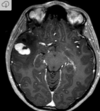

14

Q

35 anos, Masculino

A

Craniofaringioma adamantinomatoso